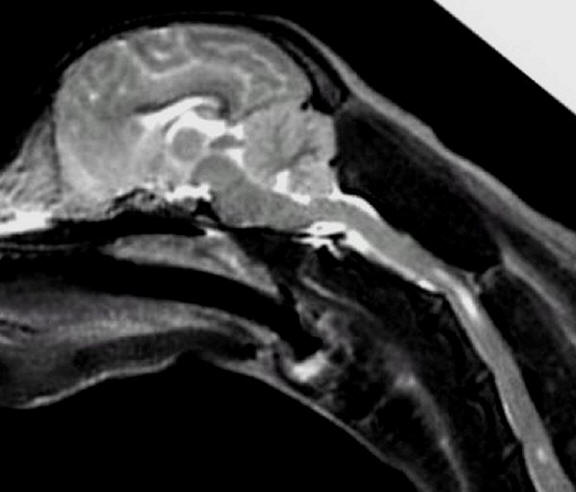

L-about

3 years old R-about 8 years old

No symptoms of SM

Little to no malformation

Little to no herniation of cerebellum

Cerebellums quite full with almost no

pinching/squashing

Medulla almost normal

No syrinxes present

3 years old

Mildest possible form of malformation, if

any

Very mild herniation of cerebellum

Cerebellum about as full as a Cavalier's

gets